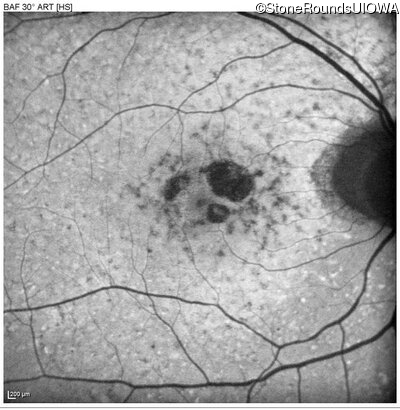

Blue Autofluorescence - Left - 20/20 -1

Exemplar